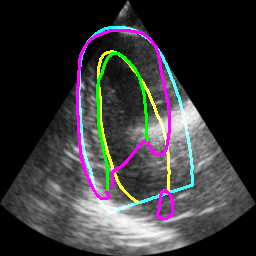

Table II displays the segmentation accuracy computed on the full dataset from patients having good and medium image quality ( patients) for the 4 algorithms described in section Sec. IV-D. Mean and standard deviation values for each metric were obtained from cross-validation on the 10 folds of the dataset. The values in bold correspond to the best scores for each metric. From these results, one can see that all the attention-based networks produced either the same, or better results than the baseline U-Net1, with AG-U-Net and LU-Net being the best performing models. Indeed, AG-U-Net obtained the overall best results for the segmentation of the LVEndo border ( value of mm and value of mm), leading to segmentation scores close but still higher than the intra-observer variability for this structure. The LU-Net-m5 approach obtained the best results for the segmentation of the LVEpi border ( value of mm and value of mm) and the lowest number of geometric outliers (%). Interestingly, these scores are either equivalent or lower than the intra-observer variability for this structure. It is also worth noting the robustness of the LU-Net model with respect to the choice of margin parameter, as margins of % and produce almost the same segmentation scores for all metrics. An illustration of the segmentation performance of the LU-Net-m5 network compared to the baseline U-Net1 model on three different cases is provided in Fig. 2.